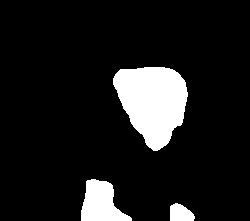

A few sample images and the corresponding masks of the polyp dataset in HyperKvasir are shown in Fig 2. The polyp images are RGB images. The masks of the polyp images are single-channel images with white () for true pixels, which represent polyp regions, and black () for false pixels, which represent clean colon or background regions. In this dataset, there are different sizes of polyps. The distribution of polyp sizes as a percentage of the full image size is presented in the histogram plot in Fig 3, and we can observe that there are more relatively small polyps compared to larger polyps. Additionally, a subset of this dataset was used to prove that the performance of segmentation models trained with small datasets can be improved using our SinGAN-Seg pipeline, and the whole dataset was used to show the effect of using SinGAN-Seg generated synthetic images instead of a large dataset which has enough data to train segmentation models. In this regard, this dataset was used for two purposes:

After training SinGAN-Seg models, we generated random samples per real image using the input scale , which is the lowest scale that uses a random noise input instead of a re-scaled input image. For more details about these scaling numbers and corresponding output behaviors, please refer to the vanilla SinGAN paper [56]. Three randomly selected training images and the corresponding first synthetic images generated using scale are depicted in Fig 4. The first column of the figure represents the real images and the ground truth mask annotated from experts. The rest of the columns represent randomly generated synthetic images and the corresponding generated mask.

In total, we have generated synthetic polyp images and the corresponding masks. SinGAN-Seg generates random samples with high variations when the input scale is . This variation can be easily recognized using the standard deviation (SD) and the mean mask images presented in Fig 5. The mean and SD images were calculated by stacking the generated mask images corresponding to the synthetic images related to a real image and calculating pixel-wise std and mean. Bright color in std images and dark color in mean images mean low variance of pixels. In contrast, dark color in std and bright color in mean images reflect high variance in pixel values. By investigating Fig 5, we see that small polyp masks have high variance compared to the large polyp mask as presented in the figure.